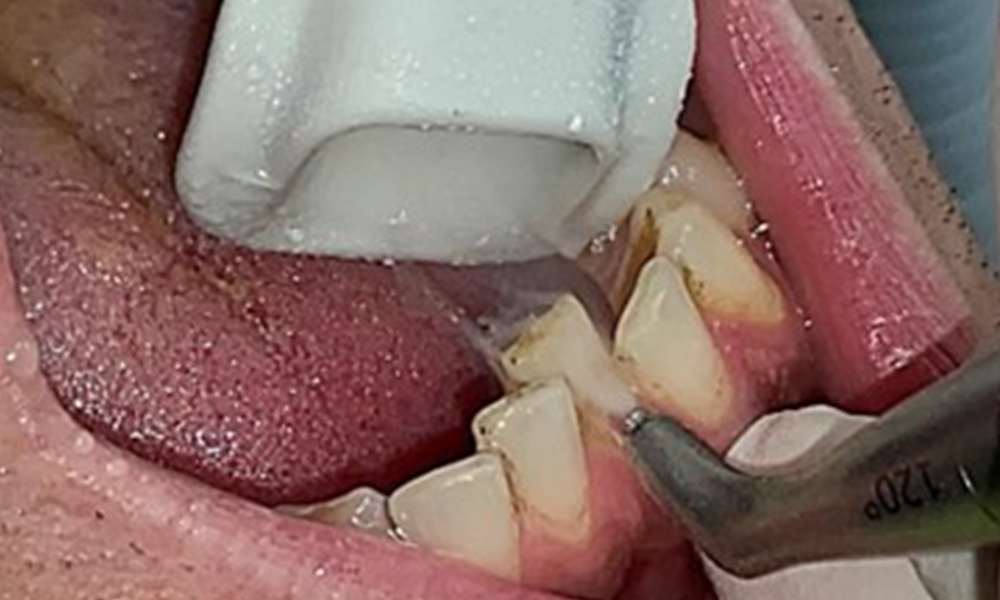

L'instruction et la motivation sont des éléments importants de ces rendez-vous. Il est important que les patients comprennent et adoptent un bon comportement en matière d'hygiène intrabuccale à domicile. L'accumulation de plaque est particulièrement évidente dans les régions cervicales (Fig. 8).

L'objectif serait de contrôler le risque de maladie en éliminant le biofilm supra-gingival et sous-gingival. Les instruments peuvent être sélectionnés en fonction des besoins du patient. Tout d'abord, le tartre et les concrétions doivent être éliminés à l'aide d'instruments ultrasoniques et/ou manuels (Fig. 10).